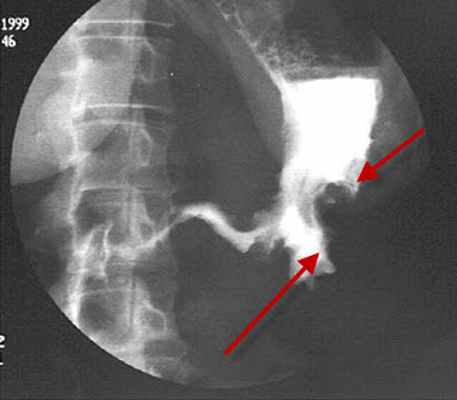

• рентгеноскопия желудка с пероральным введением контрастного препарата (сульфат бария). Один из основных методов определения локализации и протяжённости поражения стенки желудка. Наиболее важными рентгенологическими признаками рака желудка являются:

1. наличие дефекта наполнения или ниши в пределах тени желудка

2. потеря эластичности и растяжимости желудочной стенки

3. локальное отсутствие или уменьшение перистальтики в районе опухоли

4. изменение рельефа слизистой оболочки в месте расположения опухоли

5. изменение формы и размеров желудка

9. Рентгенологическая картина лейомиомы